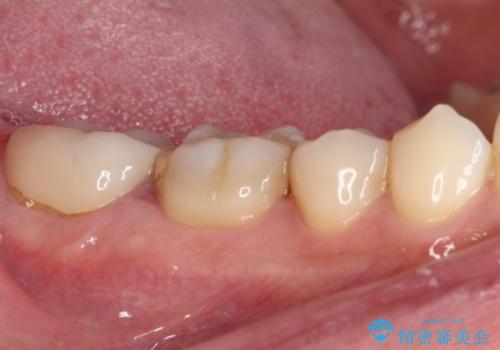

まずは仮歯に置き換え、歯周ポケットを除去するための外科処置(歯肉弁根尖側移動術)を行い、治癒を待ってセラミッククラウンにて補綴治療を行うこととしました。

外科処置後は知覚過敏症状が酷くなることが多いのですが、術後は比較的落ち着いており、スムーズに処置を進めることができました。